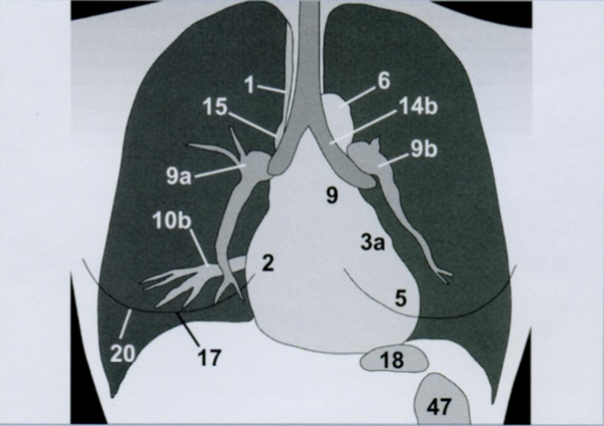

Оценка границ средостения. Оцениваем сверху вниз, начиная с правой стороны.

Найдем правый желудочек (сразу за грудиной). Сердце нормальных размеров имеет пространство между ПЖ и грудиной - загрудинное пространство (просветление на Rx органов грудной клетки в боковой проекции).

Далее ищем: дуга аорты, левый главный бронх, левая легочная артерия, легочный ствол, ушко левого предсредия, левый желудочек, верхняя полая вена, непарная вена, правая легочная артерия, правое предсердие, легочные вены.

Отметим: контур диафрагмы, контур молочной железы, газовый пузырь желудка, кишечник.

A

6 - дуга аорты

14b - левый главный бронх

9b - левая легочная артерия

9 - легочный ствол

3a - ушко левого предсредия

5 - левый желудочек

1 - верхняя полая вена

15 - непарная вена

9a - правая легочная артерия

2 - правое предсердие

10b - легочные вены.

17 - контур диафрагмы

20 - контур молочной железы

18 - газовый пузырь желудка

47 - кишечник